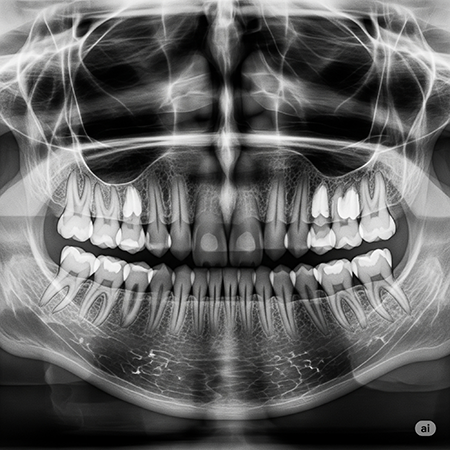

cirugía maxilofacial en Málaga

Valoracion previa y planificacion

Antes de cualquier intervención, realizamos una evaluación clínica completa, apoyada por radiografías o TAC si es necesario. Definimos un plan quirúrgico claro y resolvemos todas tus dudas.